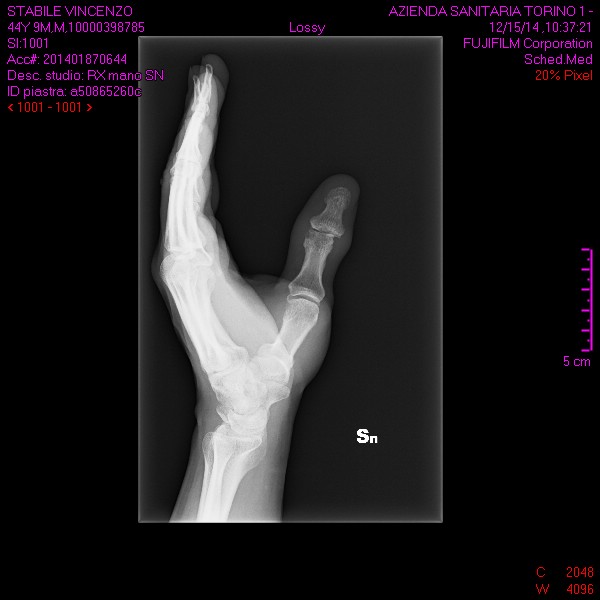

Sono sei mesi che mi sono procurato una frattura parcellare della seconda falange del pollice sinistro e non riesco a muovere come prima il dito a causa di un gonfiore ( edema?) che rende tesissima la pelle rendendo impossibile il piegamento completo.... se sforzo passivamente il dito si piega normalmente come l'altro , segno che il tendine è funzionale , ma attivamente non riesco a cusa dei liquidi presenti sull'articolazione... E' normale tutto cio' dopo sei mesi 6 ???? Grazie per il consulto.

Commento file: queste sono le radiografie fatte giorno 15 dicembre 2014

buonasera, visto lastre. direi che il tempo è eccessivo.

è oppurtuno effettuare una rmn e una visita da un altro medico per avere confronto di pareri e poi valutare.

dopo sei mesi è anomalo che non ci sia un inizio di calcificazione.

una cosa è articolazione, un'altra è la frattura che intende lei.